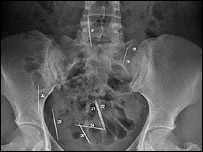

Radiografia cedida pelo Richland International Hospital

Os médicos dizem que a remoção das agulhas será um processo longo

Radiografias mostraram a presença das agulhas - algumas das quais haviam penetrado órgãos vitais como pulmões, fígado e rins.

Uma agulha quebrou em três pedaços em seu cérebro.

Uma equipe internacional de médicos baseados em um hospital no sul da província chinesa de Yunan agora está discutindo qual é a melhor forma de remover as agulhas.

Os médicos disseram que o procedimento será demorado e complicado que exigirá várias cirurgias.